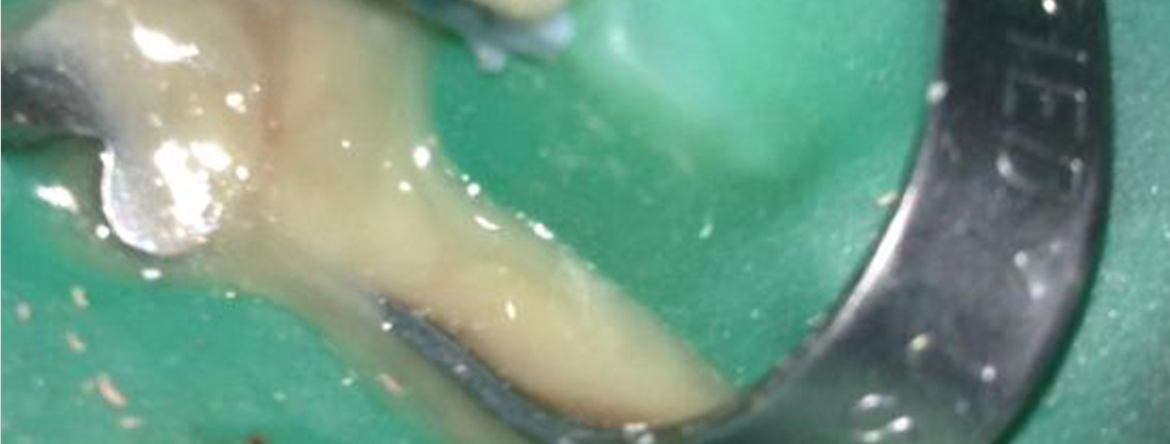

A endodontia é das áreas da medicina dentária que mais evoluiu nos últimos anos. Várias técnicas e equipamentos permitem, hoje em dia, que as taxas de sucesso sejam cada vez mais elevadas, tornando os procedimentos mais previsíveis.

Conhecer a morfologia e a fisiologia do complexo pulpo-dentinário e as suas relações com os tecidos adjacentes, torna-se imperioso para um correto diagnóstico e para estabelecer o correto plano de tratamento. Só assim poderemos aplicar aos nossos pacientes os tratamentos adequados.